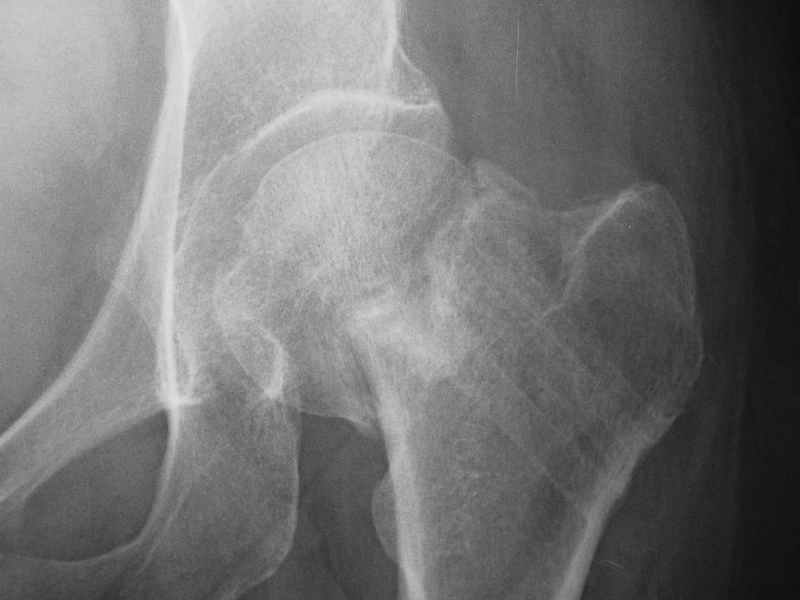

При явно выраженном варусе и флексионных состояниях после сросшихся переломов шейки бедра у молодых рекомендуется реконструктивная операция по исправлению варуса для предотвращения раннего деформирующего артроза, приводящего в результате переднего импинжмента, как показано на снимке.

Межвертельная вальгусная остеотомия представляет наименьший риск среди всех реконструктивных операции в проксимальной части бедра, создавая наилучшие биомеханические условия (увеличивается сила абдукторов, увеличивается сила суставной реакции, уменьшение рычага моментов абдукторов и уменьшение скольжения) и при меньшем риске повреждения кровоснабжения головки, где обычно в 90% случаях достигается отличный результат при применении метода для лечения ложных суставов шейки бедра.

После вальгусных межвертельных операции уже через 2 месяца можно получить результат (predicted outcome), а когда после спонгиозных шурупов результат надо ждать не менее 3-4 месецев, а иногда при свежих переломах сращение в шейке бедра наступает не раньше 5-6 месяцев, тем более при таком варусе спонгиозная фиксация не гарантирует дальнейшее скольжение перелома и ухудшения варуса.

По моему, 120 градусная угловая пластина blade plate решит все проблемы, только необходим предварительный расчет угла остеотомии, и во время фиксации пластины не забыть латерализацию бедра, иначе ось конечности от варуса перейдёт в нежелательный вальгус.

Для предупреждения вальгуса клинок пластины берется на 10-12 мм длиннее чем предварительный туннель на головке, тогда во время

фиксации за бедро пластина автоматически приблизит бедро и происходит латерализация бедра. Если между клинком и латеральным кортексом бедра положить частицу кости от остеотомии тогда образуется дополнительная компрессия на фокусе несращения.

Здесь мои диаграммы для расчета угла остеотомии и латеризации бедра.